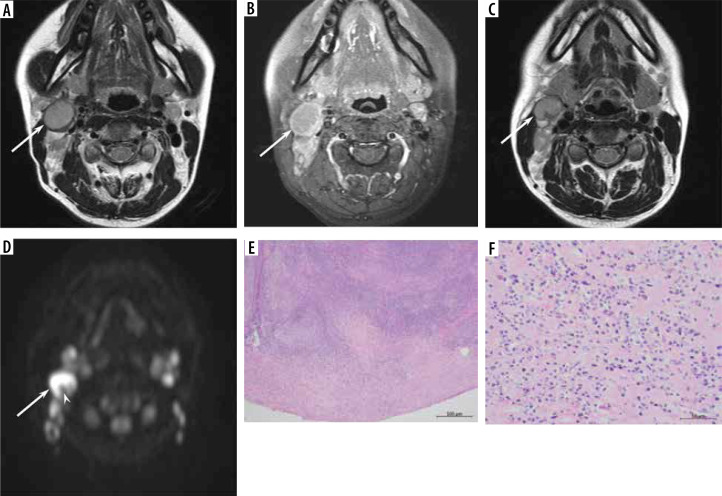

Results: The maximum diameter (22.4 ± 6.9 vs. 33.3 ± 16.0 mm, p < 0.01), minimum diameter (15.8 ± 3.6 vs. 22.3 ± 8.5 mm, p < 0.01), and SUVmax (6.9 ± 2.7 vs. 12.8 ± 8.0, p < 0.01) of the lesion were lower in reactive lymphadenitis than in nodal lymphoma, respectively. T2-hypointense-thickened capsules > 2 mm (46% vs. 14%, p < 0.05) and T2-hypointense areas converging to the periphery (15% vs. 0%, p < 0.05) were more frequently observed in reactive lymphadenitis than in nodal lymphoma, respectively. Hilum of nodes on T2-weighted images (54% vs. 22%, p < 0.05) and diffusion-weighted images (69% vs. 30%, p < 0.05) were more frequently demonstrated in reactive lymphadenitis than in nodal lymphoma, respectively.

Conclusions: Reactive lymphadenitis had a smaller size and lower SUVmax. The presence of T2-hypointense-thickened capsules, T2-hypointense areas converging to the periphery, and hilum of nodes were signs of reactive lymphadenitis.